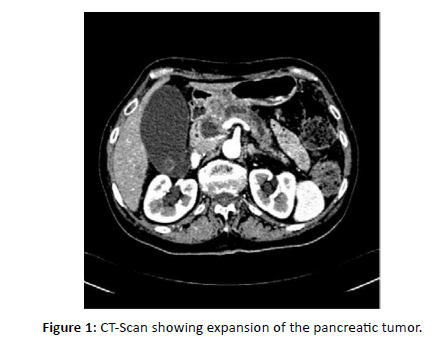

A 53-year-old woman with a history of breast cancer was initially diagnosed in 2011 with right-sided invasive ductal carcinoma located at the upper-quadrant junction. Pathology showed pT2 (25 mm), pN1 (1/15), M0, SBR grade 2, ER-positive, and HER2 3+. She underwent breast-conserving surgery followed by adjuvant chemotherapy (six cycles of docetaxel-trastuzumab), trastuzumab maintenance until July 2012, adjuvant radiotherapy, and endocrine therapy with tamoxifen. Tamoxifen was discontinued after two years due to recurrent phlebitis. In September 2014, she underwent bilateral adnexectomy and began letrozole, which was soon discontinued because of severe arthralgia. In February 2020, she presented with pruritic jaundice related to a pancreatic head mass complicated by acute pancreatitis. Histopathological analysis of the pancreatic mass confirmed metastatic carcinoma with neuroendocrine differentiation, with an immunophenotype consistent with breast origin (ER-positive, PR-negative, HER2-negative) [Figure 3]. A CT scan on March 5, 2020, showed a slight expansion of the pancreatic tumor [Figure 1].

Figure 1: CT-Scan showing expansion of the pancreatic tumor.